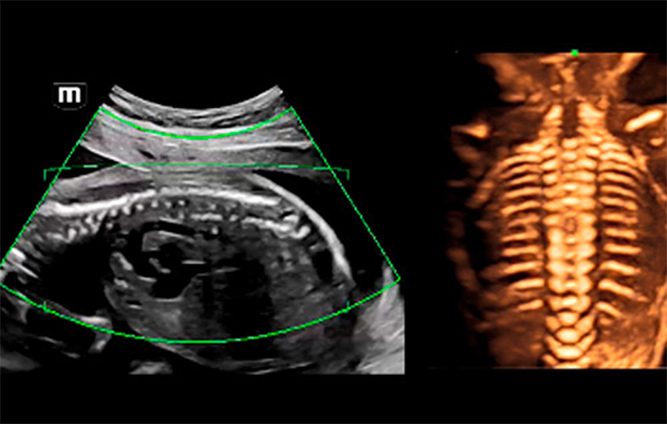

Afin de rĂŠduire la dĂŠpendance Ă l'utilisateur et d'amĂŠliorer l'efficacitĂŠ du diagnostic, Mindray a dĂŠveloppĂŠ une interaction?3D/4D innovante basĂŠe sur des scĂŠnarios cliniques d'examen ĂŠchographique?3D tels que le cerveau, le visage, la colonne vertĂŠbrale et les os longs du f?tus, ce qui permet d'automatiser l'identification de la vue, l'optimisation de l'imagerie, l'acquisition des plans et la quantification en un seul clic. Le flux de travail est vĂŠritablement automatique tout au long de la procĂŠdure, et apporte une grande confiance envers le diagnostic pour de meilleurs soins au patient.

Images ĂŠchographiques?3D/4D de la colonne vertĂŠbrale du f?tus